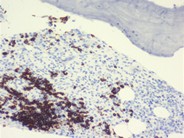

Scattered mast cells (arrows) with variable granulation are shown in this bone marrow aspirate.